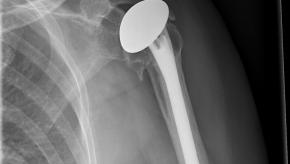

Read ArticleDurability of Total Shoulder Arthoplasty

A systematic review of the outcomes of total shoulder replacements (TSR), humeral hemiarthroplasties, and reverse total shoulder replacements finds that approximately 90% of shoulder replacements last for longer than 10 years with good patient-reported outcomes.